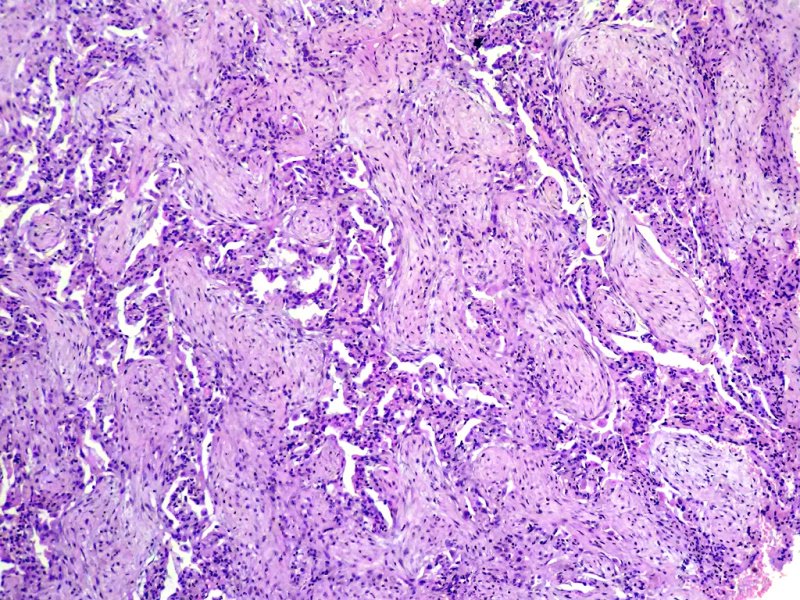

Próstata. Tumor estromal de potencial maligno incierto. Tinción HE.

Anapat tweet mediaAnapat tweet mediaAnapat tweet media